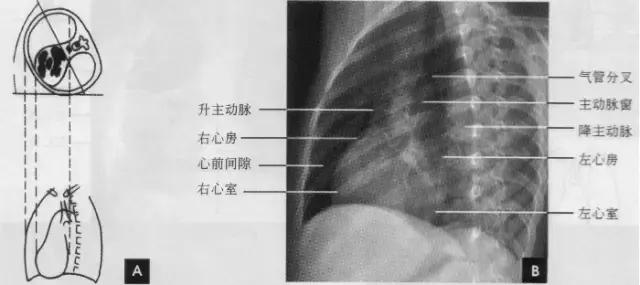

(四)左侧位

心影从后上向前下倾斜,心前缘下段为右心室前壁,上段则由右心室漏斗部与肺动脉主干构成,再苣上为升主动脉前壁,直向上走行。这些结构与翦髓壁之间的三角形透亮区称为胸骨后区。心后缘上中段由左心房构成,下段则由左心室构成。心后下缘、食管与膈之间的三角形间隙,为心后食管前间隙(如下图)。